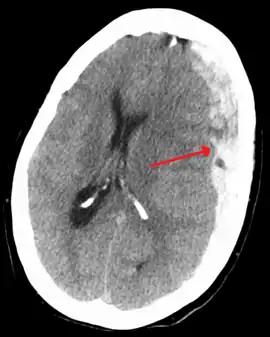

| Subdural hematoma as marked by the arrow with significant midline shift | |

On a CT scan, subdural hematomas are classically crescent-shaped, with a concave surface away from the skull. However, they can have a convex appearance, especially in the early stages of bleeding. This may cause difficulty in distinguishing between subdural and epidural hemorrhages. A more reliable indicator of subdural hemorrhage is its involvement of a larger portion of the cerebral hemisphere. Subdural blood can also be seen as a layering density along the tentorium cerebelli. This can be a chronic, stable process, since the feeding system is low-pressure. In such cases, subtle signs of bleeding—such as effacement of sulci or medial displacement of the junction between gray matter and white matter—may be apparent.